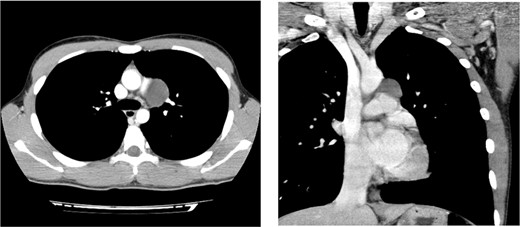

A 17-year-old man was admitted to the hospital for surgical resection of an enlarging mediastinal cystic mass. A routine medical examination carried out at a junior high school detected an abnormal shadow on chest radiograph and chest computed tomography (CT) scan showed a cystic lesion (25 × 23 mm) located on the lateral side of the aortic arch in the middle mediastinum with no other abnormalities. Gradual growth of the cystic lesion was discovered by a CT scan during follow-up over 3 years with the lesion reaching 38 × 33 mm in size (Fig. 1). The patient was asymptomatic with no significant findings on physical examination. An electrocardiogram (ECG) on admission showed right bundle branch block (RBBB) with no other abnormal findings, and spirometry showed normal respiratory function.

Preoperative chest CT scan showing a cystic mediastinal mass adjacent to the left pulmonary artery and aortic arch.